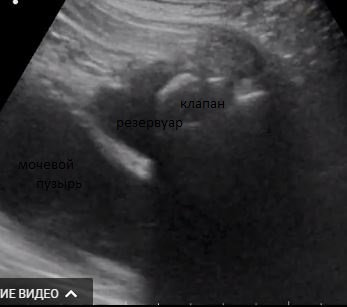

Пациент 1949 г.р., жалобы на периодическое недержание мочи. 10 лет назад прооперирован по поводу аденомы простаты.

Образование остается.

Дивертикул мочевого пузыря? серозоцеле?

смущает гиперэхогенное округлое в полости справа, в верхней части.

Смотрел. Без потоков. В постановке диагноза помог только анамнез.